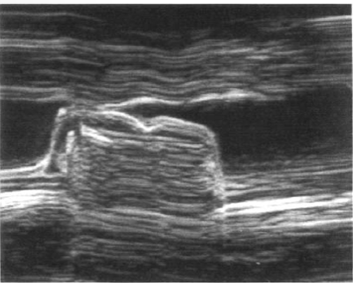

what is characteristic finding in mitral stenosis m mode?

decreased E/F slope